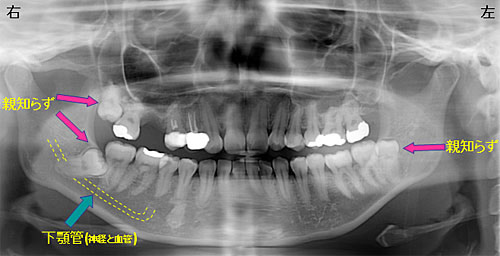

- MANDIBULAR

- 下顎管について

- ●下顎の骨の中には「下顎管」と呼ばれる神経と血管が通っている管が存在します。

- ●親知らずがこの管とレントゲン上で近い場合や、重なっている場合は神経麻痺や、損傷の可能性がある為、当院での抜歯が困難な場合があります。